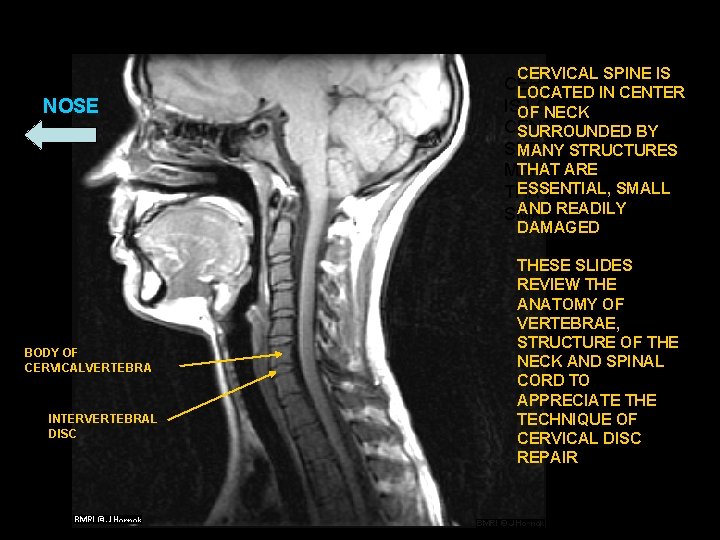

CERVICAL SPINE IS NOSE CERVICAL SPINE LOCATED IN CENTER ISOF LOCATED IN NECK CENTER OF NECK SURROUNDED BY MANY STRUCTURES THAT STRUCTURES ARE MANY ESSENTIAL, SMALL THAT ARE ESSENTIAL, AND READILY SMALL AND FRAGILE DAMAGED BODY OF CERVICALVERTEBRA INTERVERTEBRAL DISC THESE SLIDES REVIEW THE ANATOMY OF VERTEBRAE, STRUCTURE OF THE NECK AND SPINAL CORD TO APPRECIATE THE TECHNIQUE OF CERVICAL DISC REPAIR